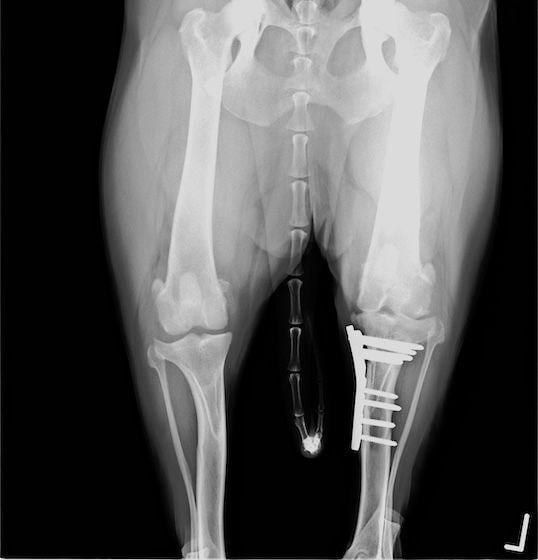

雑種犬 推定10歳 避妊雌

本症例は、走った後に左後肢を挙上していることを主訴に来院されました。触診時に左膝関節のクリック音を聴取、レントゲン検査にて左脛骨の前方変位が認められました。術中に、前十字靱帯の断裂及び内側半月板の損傷、内側の軟部組織の顕著な腫脹を確認。半月板切除、TPLOを実施しました。周囲組織への炎症の波及もあったため回復に時間を要しておりますが、徐々に跛行頻度は減少傾向にあり、現在も経過観察中です。術前に約29°あったTPAは術後に約10°まで矯正されました。

術前写真

術後写真

手術前後のTPA(脛骨高平部の角度)を測定しています。

約29°から約10°へ矯正されています。